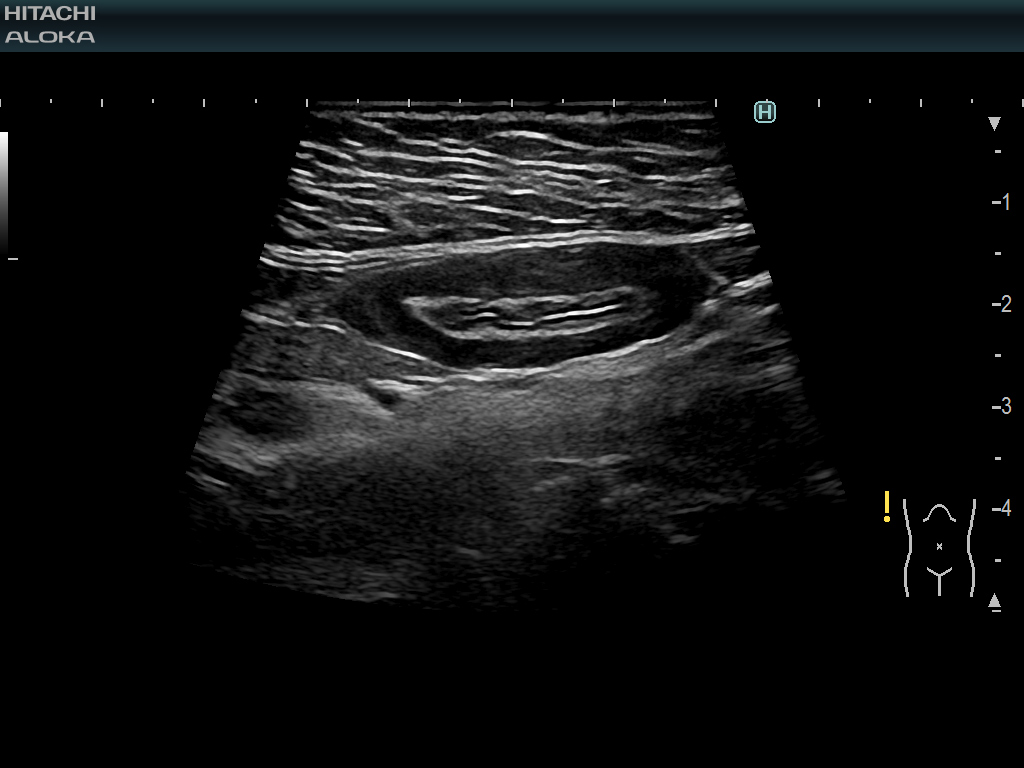

4G CMUT는 심박 기관 및 혈관을 포함한 전신 검사에 사용할 수 있습니다. 이러한 경우 장 벽의 두께와 염증 과정을 묘사합니다.